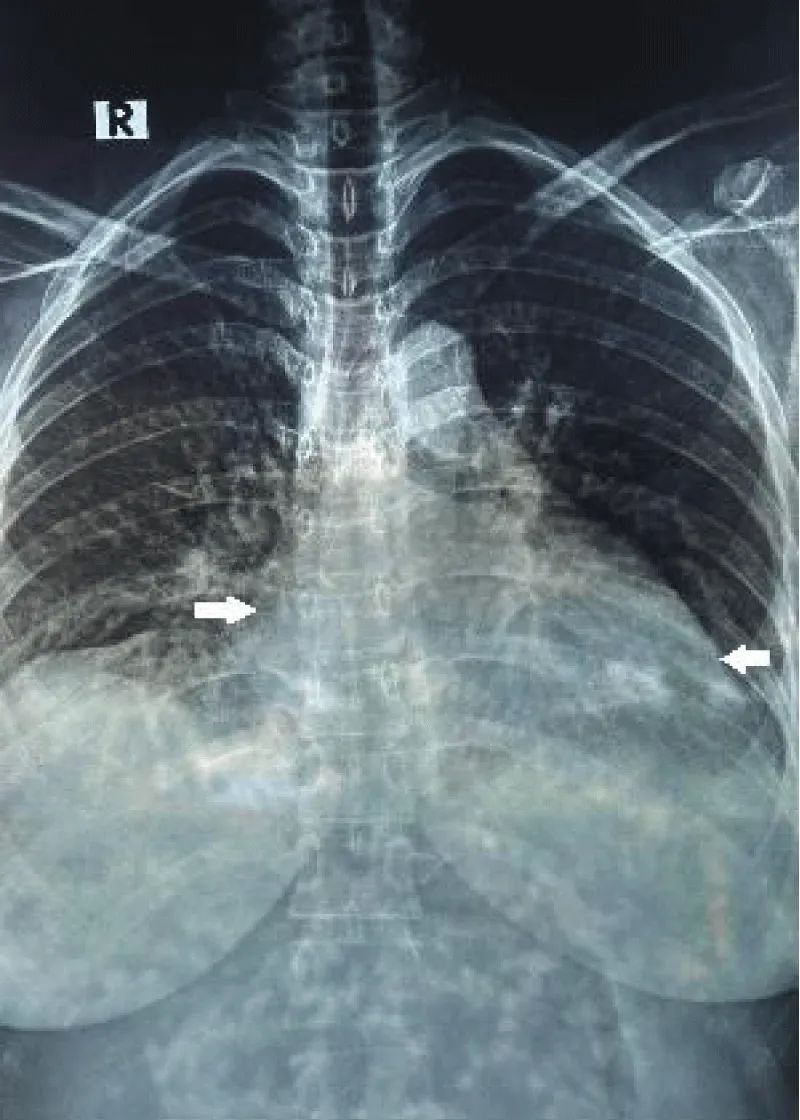

Her complete blood count, lipase, CRP, troponin, electrolytes, creatinine, calcium, magnesium, alkaline phosphatase, and urine routine microscopic examinations were unremarkable. Her bicarbonate level was 17.0 mmol/L and revealed an anion gap of 32.34. The lipid profile was abnormal for triglycerides of 984 mg/dL. Chest x-ray showed cardiomegaly (Figure 2). An echocardiogram showed dilated cardiomyopathy, mild MR, TR, and LV systolic dysfunction-ejection fraction (EF) of 45% (Figure 3). The patient was shifted to the general ward after 2 days upon stabilization. A diagnosis of acute severe pancreatitis was considered initially based on the clinical presentation with peripartum cardiomyopathy as the differential diagnosis. Based on her clinical signs, symptoms, and results of additional tests, the diagnosis of peripartum cardiomyopathy was made. After a consultation with the cardiology department, she was initiated on diuretics, ACEi, Beta Blockers, iron supplementation, empagliflozin, thiamine, and statin. Careful counseling was done regarding contraception and future pregnancies. She was advised to follow up one month later.

Download Image

Figure 2: Chest X-ray showing cardiomegaly (white arrows, showing increased diameter).